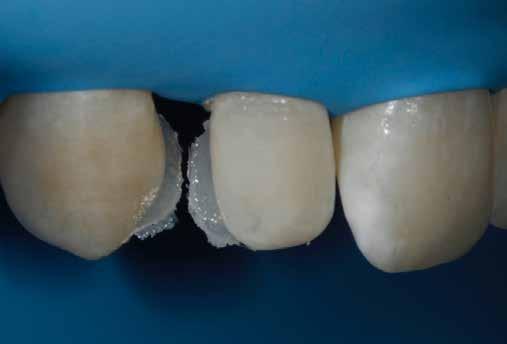

1. A kofferdámmal a legkritikusabb területen, amely megfelel a zenit és a kiemelkedési profilnak, RETRAKCIÓT hoz létre, amit semmilyen wax-uppal nem lehet megtenni (5. ábra).

2. A bukkális növekmény stabil kompozittal létrehozott szabadkézi felépítése, amely követi az Ön közvetlen látását és a fog megjelenését, ugyanolyan pontosan meghatározza a FORMÁT, mint egy wax-up. Más szóval, ez egy direkt wax-up.

3. A hátsó mátrixok OPTIMÁLJÁK az előzőleg felépített formát, és létrehozzák az ideális érintkezési pontot.

4. A hátsó kitöltés minden hézagot kiküszöböl, és tökéletes ZÁRÓDÁS-t hoz létre, különösen a restauráció legapikálisabb részén.

2. eset: Egyszínű restauráció egy mikrodiasztémán, ahol a viasz nem kivitelezhető (1 óra ülésidő)

3. eset: Diasztéma zárása, dentin és zománc rétegezéssel az opacitás és a metszőfogtörések korrekciója érdekében (1 óra székben töltött idő)